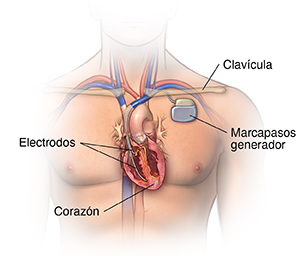

Un marcapasos es un dispositivo pequeño que se implanta en el pecho. Envía señales eléctricas para iniciar o regular el ritmo cardíaco lento. Suele colocarse en el pecho, debajo de la clavícula. Se puede usar un marcapasos si el marcapasos natural del corazón (el nódulo sinoauricular) no funciona como debería y produce un ritmo o una frecuencia cardíaca lenta o si las vías eléctricas están obstruidas.

¿Cuáles son las partes de un marcapasos o un DAI?

Un marcapasos o un DAI típicos tienen tres partes principales:

Un generador de pulsos con batería sellada de litio. El generador de pulsos envía las señales eléctricas que hacen latir el corazón o envía una descarga eléctrica. La mayoría de los generadores también pueden recibir señales enviadas por el propio corazón y responder a dichas señales.

Un cable o más. Son cables flexibles y con aislamiento. Los cables conducen las señales eléctricas entre el corazón y el generador de pulsos. Un extremo del cable se conecta al generador de pulsos y el extremo del electrodo del cable se coloca en el corazón. En el caso del marcapasos biventricular, los cables se colocan en ambos ventrículos.

Electrodos. Se ubican en cada cable.

El proveedor de atención médica le hará una incisión pequeña debajo de la clavícula. Colocará el cable o los cables del marcapasos/DAI en el corazón a través de un vaso sanguíneo que pasa por debajo de la clavícula. Una vez que el cable esté en su posición, el proveedor de atención médica lo probará para asegurarse de que esté en el lugar correcto y funcione. A continuación, conectará el cable al generador (batería), que se coloca debajo de la piel a través de la incisión ya hecha. El proveedor de atención médica cerrará la incisión con puntos, grapas o pegamento quirúrgico (adhesivo) y colocará un vendaje. Una vez finalizado el procedimiento, tendrá un período de recuperación de varias horas.